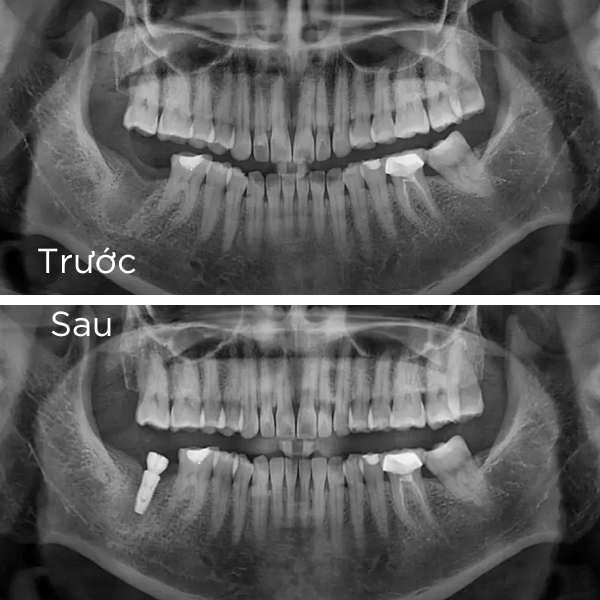

là phương pháp phục hồi răng mất tiên tiến, sử dụng trụ chụ chân răng nhân tạo – Implant từ titanium cấy vào xương hàm để thay thế chân răng đã mất. Sau đó, một mão răng sứ được gắn lên trụ, tạo ra chiếc răng mới với hình dáng và chức năng giống như răng thật.